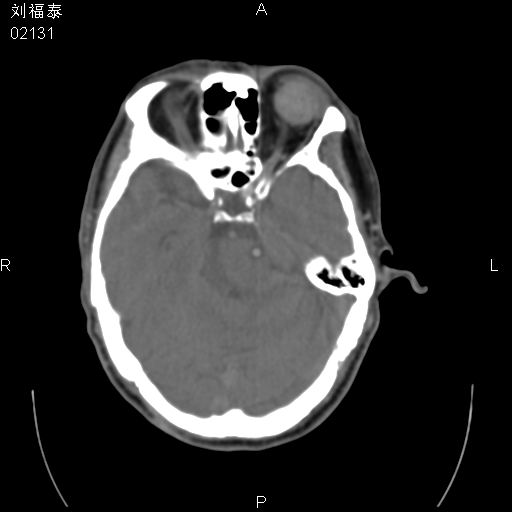

以下是引用余辉在2008-3-4 14:00:00的发言:[br]考虑左眼球黑色素瘤或血管源性肿瘤可能性大,建议增强检查

以下是引用余辉在2008-3-4 14:00:00的发言:[br]考虑眼球黑色素瘤或血管源性肿瘤可能性大,建议增强检查

以下是引用zsl6918在2008-3-4 15:08:00的发言:[br]现有征象只能提示球内出血,视网膜脱落,至于是否为肿瘤性病变需mri检查。